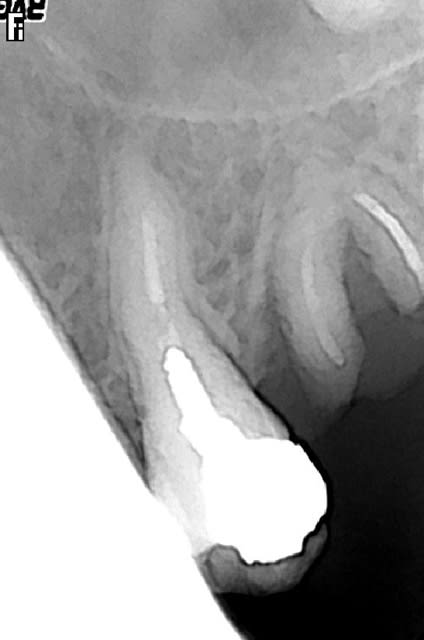

Est ce un fait exprès? Mais depuis mon retour, presque toute ma pratique tourne autour des reprises ENDO, et là, il faut que j'avoue toute l'admiration que j'ai pour les endodontistes exclusifs, c'est tout bonnement éreintant cette discipline, surtout lorsqu'on tombe sur des os!

Est-ce un fruit du hasard, mais les interventions que j'ai négociées représentent pratiquement tous les cas de figure qu'a traité Stéphane:

- fausse route bouchée au MTA

-instrument fracturé impossible à retirer, je suis passée à côté et je l'ai noyé dans la gutta chaude.